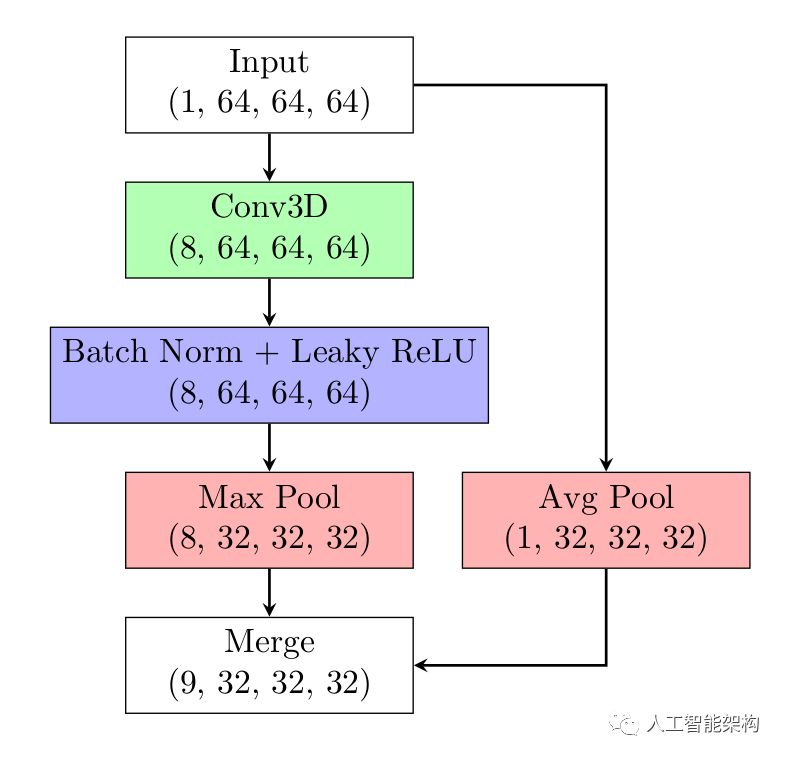

神经网络模型的输入数据为的CT,训练数据集包含了LUNA16的带注释的数据和LUNA16的假阳性数据。模型由5个卷积块(conv block)组成,以及全局最大池化层和带softplus激活函数的非负回归层。为了模型能在不同尺度上捕获信息,原始输入通过降采样(downsample)的方式输入至模型的每一层。由于模型的目标为非负的,因此使用softplus激活函数。3D卷积大小为

,池化层采用步长为2的

的kernel。在每次卷积和池化后进行批量归一化,随后进行降采样处理。模型使用75%的数据用于训练,25%的数据用于测试,大多数模型使用Leaky ReLU激活函数。其中,用于检测异常的模型使用90%的非结节数据和10%的结节数据训练,而用于预测结节属性的模型与此相反。

上图为一个卷积块(conv block)的结构。